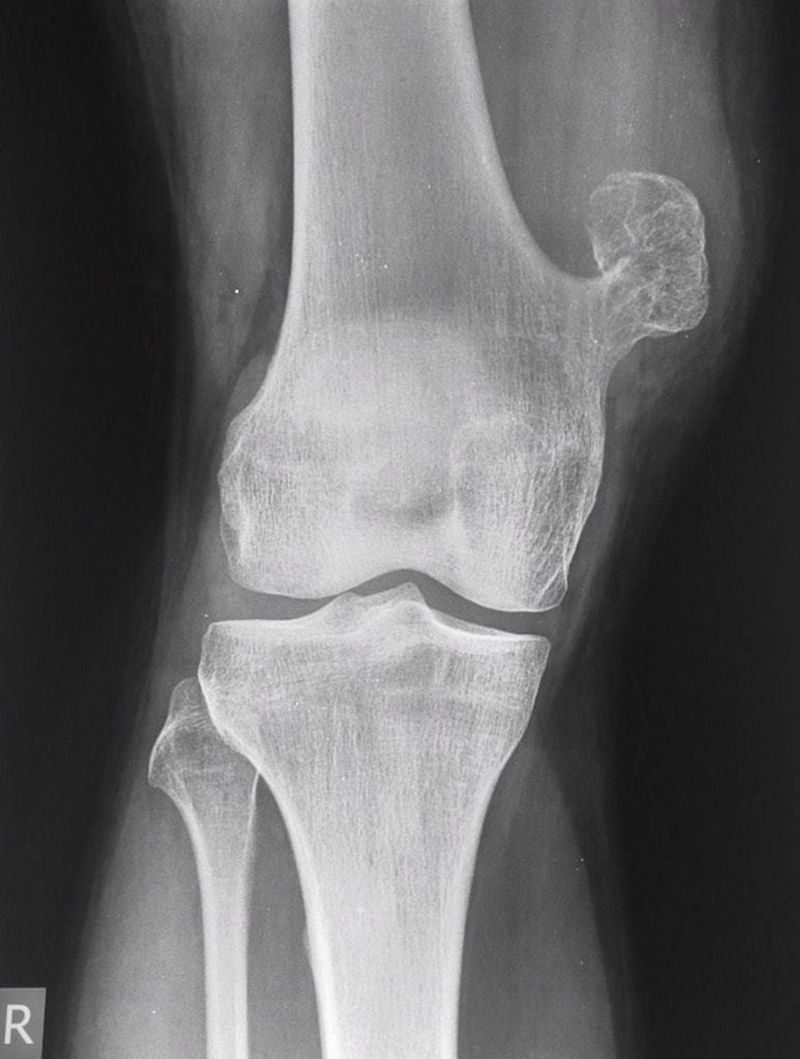

Osteochondroma

Exostosis

Distalfemur